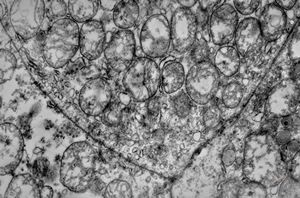

M,51y. | tubular convolution - scrotal sarcoma

M,51y. | tubular convolution - scrotal sarcoma

F,6y. | tubular convolution, perhaps obliquely sectioned - epithelial tumor of the lip